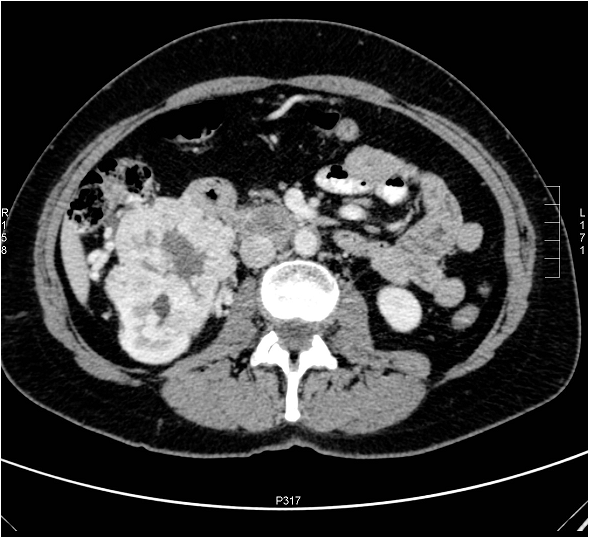

Image

Figure 9. Axial CT images show an extensive tumor in the bladder fundus.